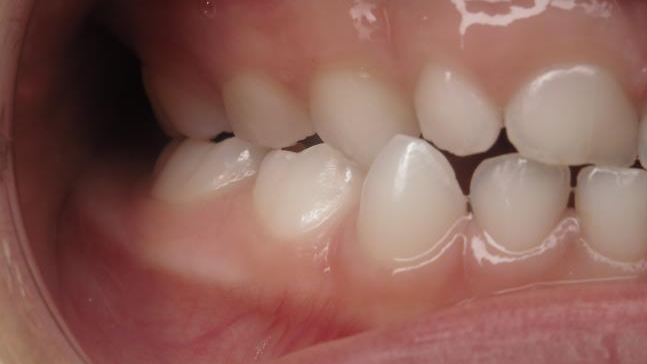

25. bout à bout anterieur 6 ans

dents du haut bout à bout par rapport à celle du bas

appareillage mobile pendant 22 mois